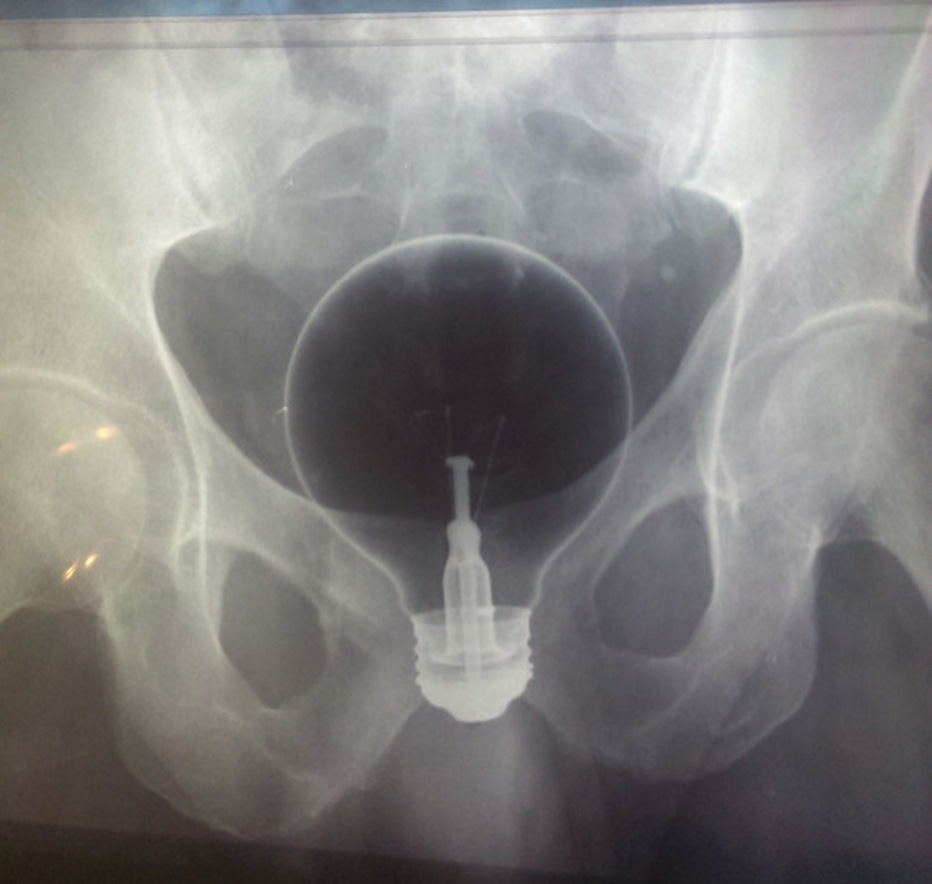

7. Une ampoule

« Ma mère se souviendra toujours du gars qui s’est entré une ampoule dans le derrière. Je lui ai demandé comment c’est sorti, elle m’a répondu : « Avec beaucoup de difficulté. » »